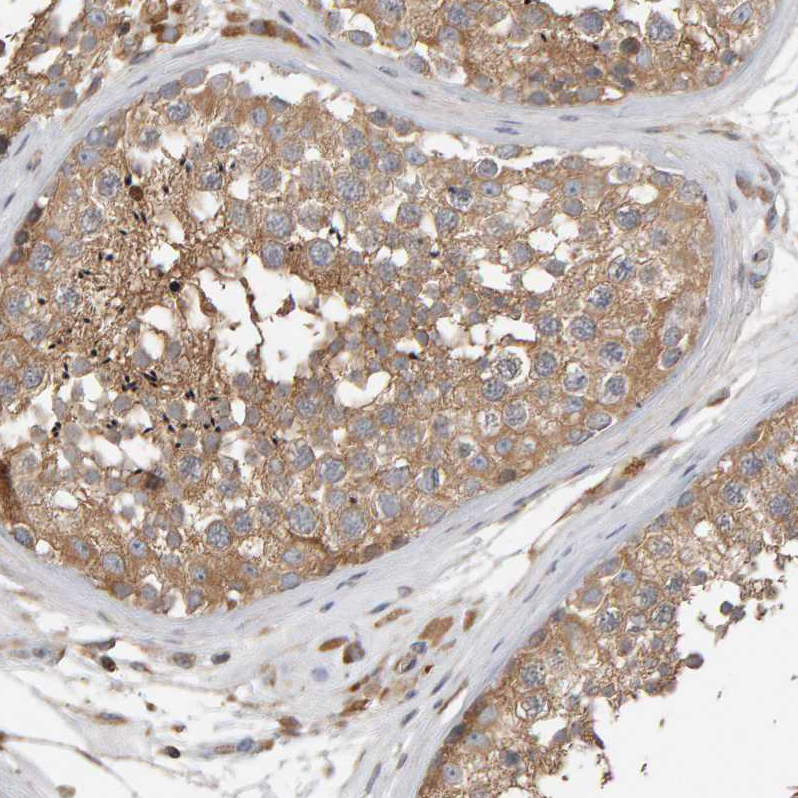

Immunohistochemical staining of human testis shows moderate cytoplasmic positivity in cells in seminiferous ducts.